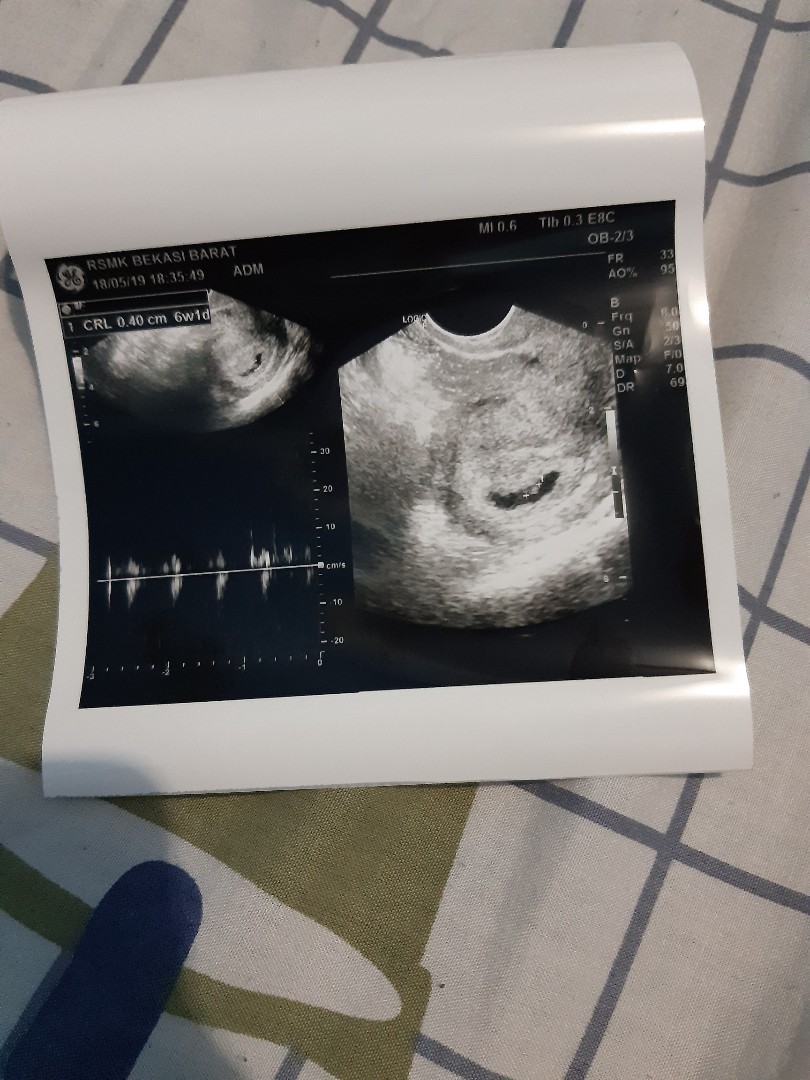

USG 5 Week

Ada yg pernah ngalamin gak bun? Sya hamil 5 week kemarin saya mengalami flek akhirnya saya periksa ke dokter lalu di USG, dan ternyata pas diusg kantung rahimnya gak normal katanya seharusnya yg normal itu bulat, nah punyaku ini lonjong bun, takutnya nanti janinnya gak bisa berkembang, tapi sama dokter masih diusahain dikasik obat penguat kandungan. lalu suruh kontrol lagi 1 minggu kemudian apakah janinnya berkembang atau tdk, klo tdk terpaksa hrus di kuret. Dan udah seminggu ini aku tetep keluar flek bun tapi dikit". Tolong berbagi pengalaman bund jika ada yg seperti saya.